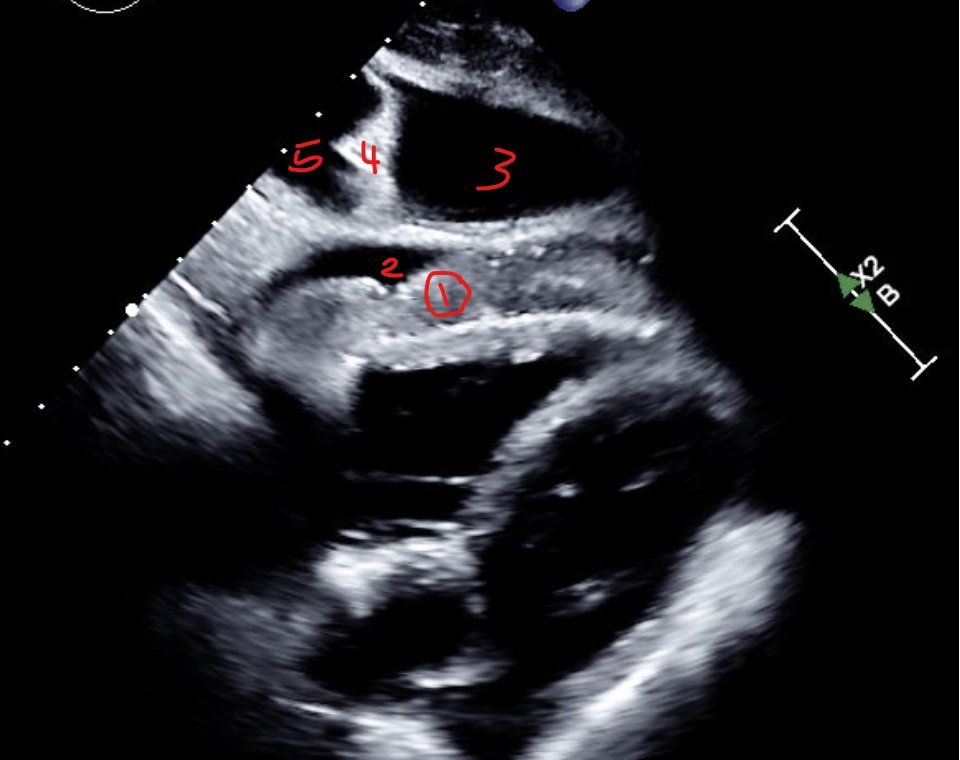

Decoding #VExUS: a practical guide for excelling in #POCUS assessment of venous congestion. - Taweevat “Games” Assavapokee & team #FOAMed #Nephpearls 🔗 theultrasoundjournal.springeropen.com/articles/10.11…

This 2021 review on #POCUS for hemodynamic assessment, published in ASN Kidney360, remains one of the most cited on this topic (💯+). Grateful for the continued support; especially proud to have co-authored it with Nathaniel Reisinger and Eduardo R Argaiz, co-founders of IAPN, back when